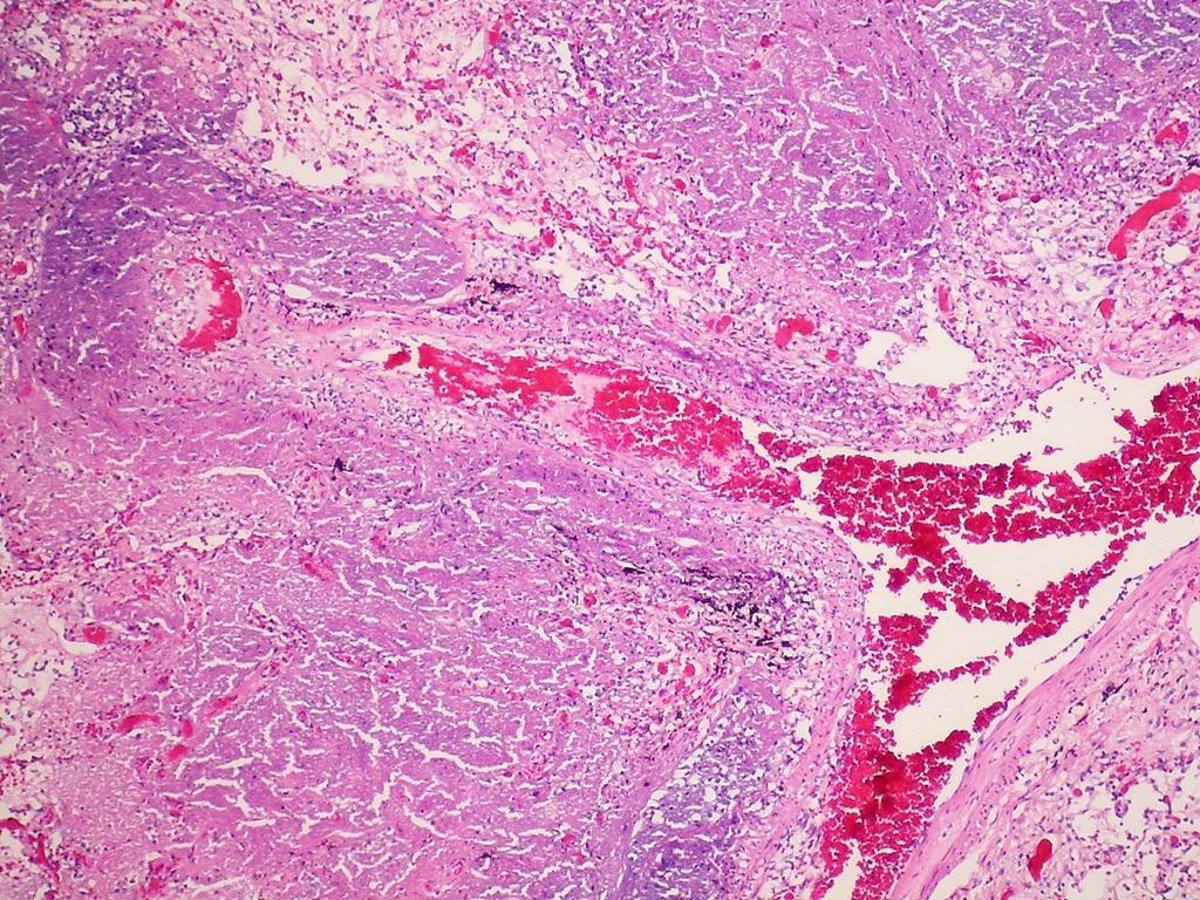

Tuberculosis

FLICKER/ PULMONARY PATHOLOGY

La tuberculosis afecta normalmente a los pulmones, si bien la bacteria la origina suele desarrollarse tan solo en las personas que tienen un sistema inmunológico debilitado.